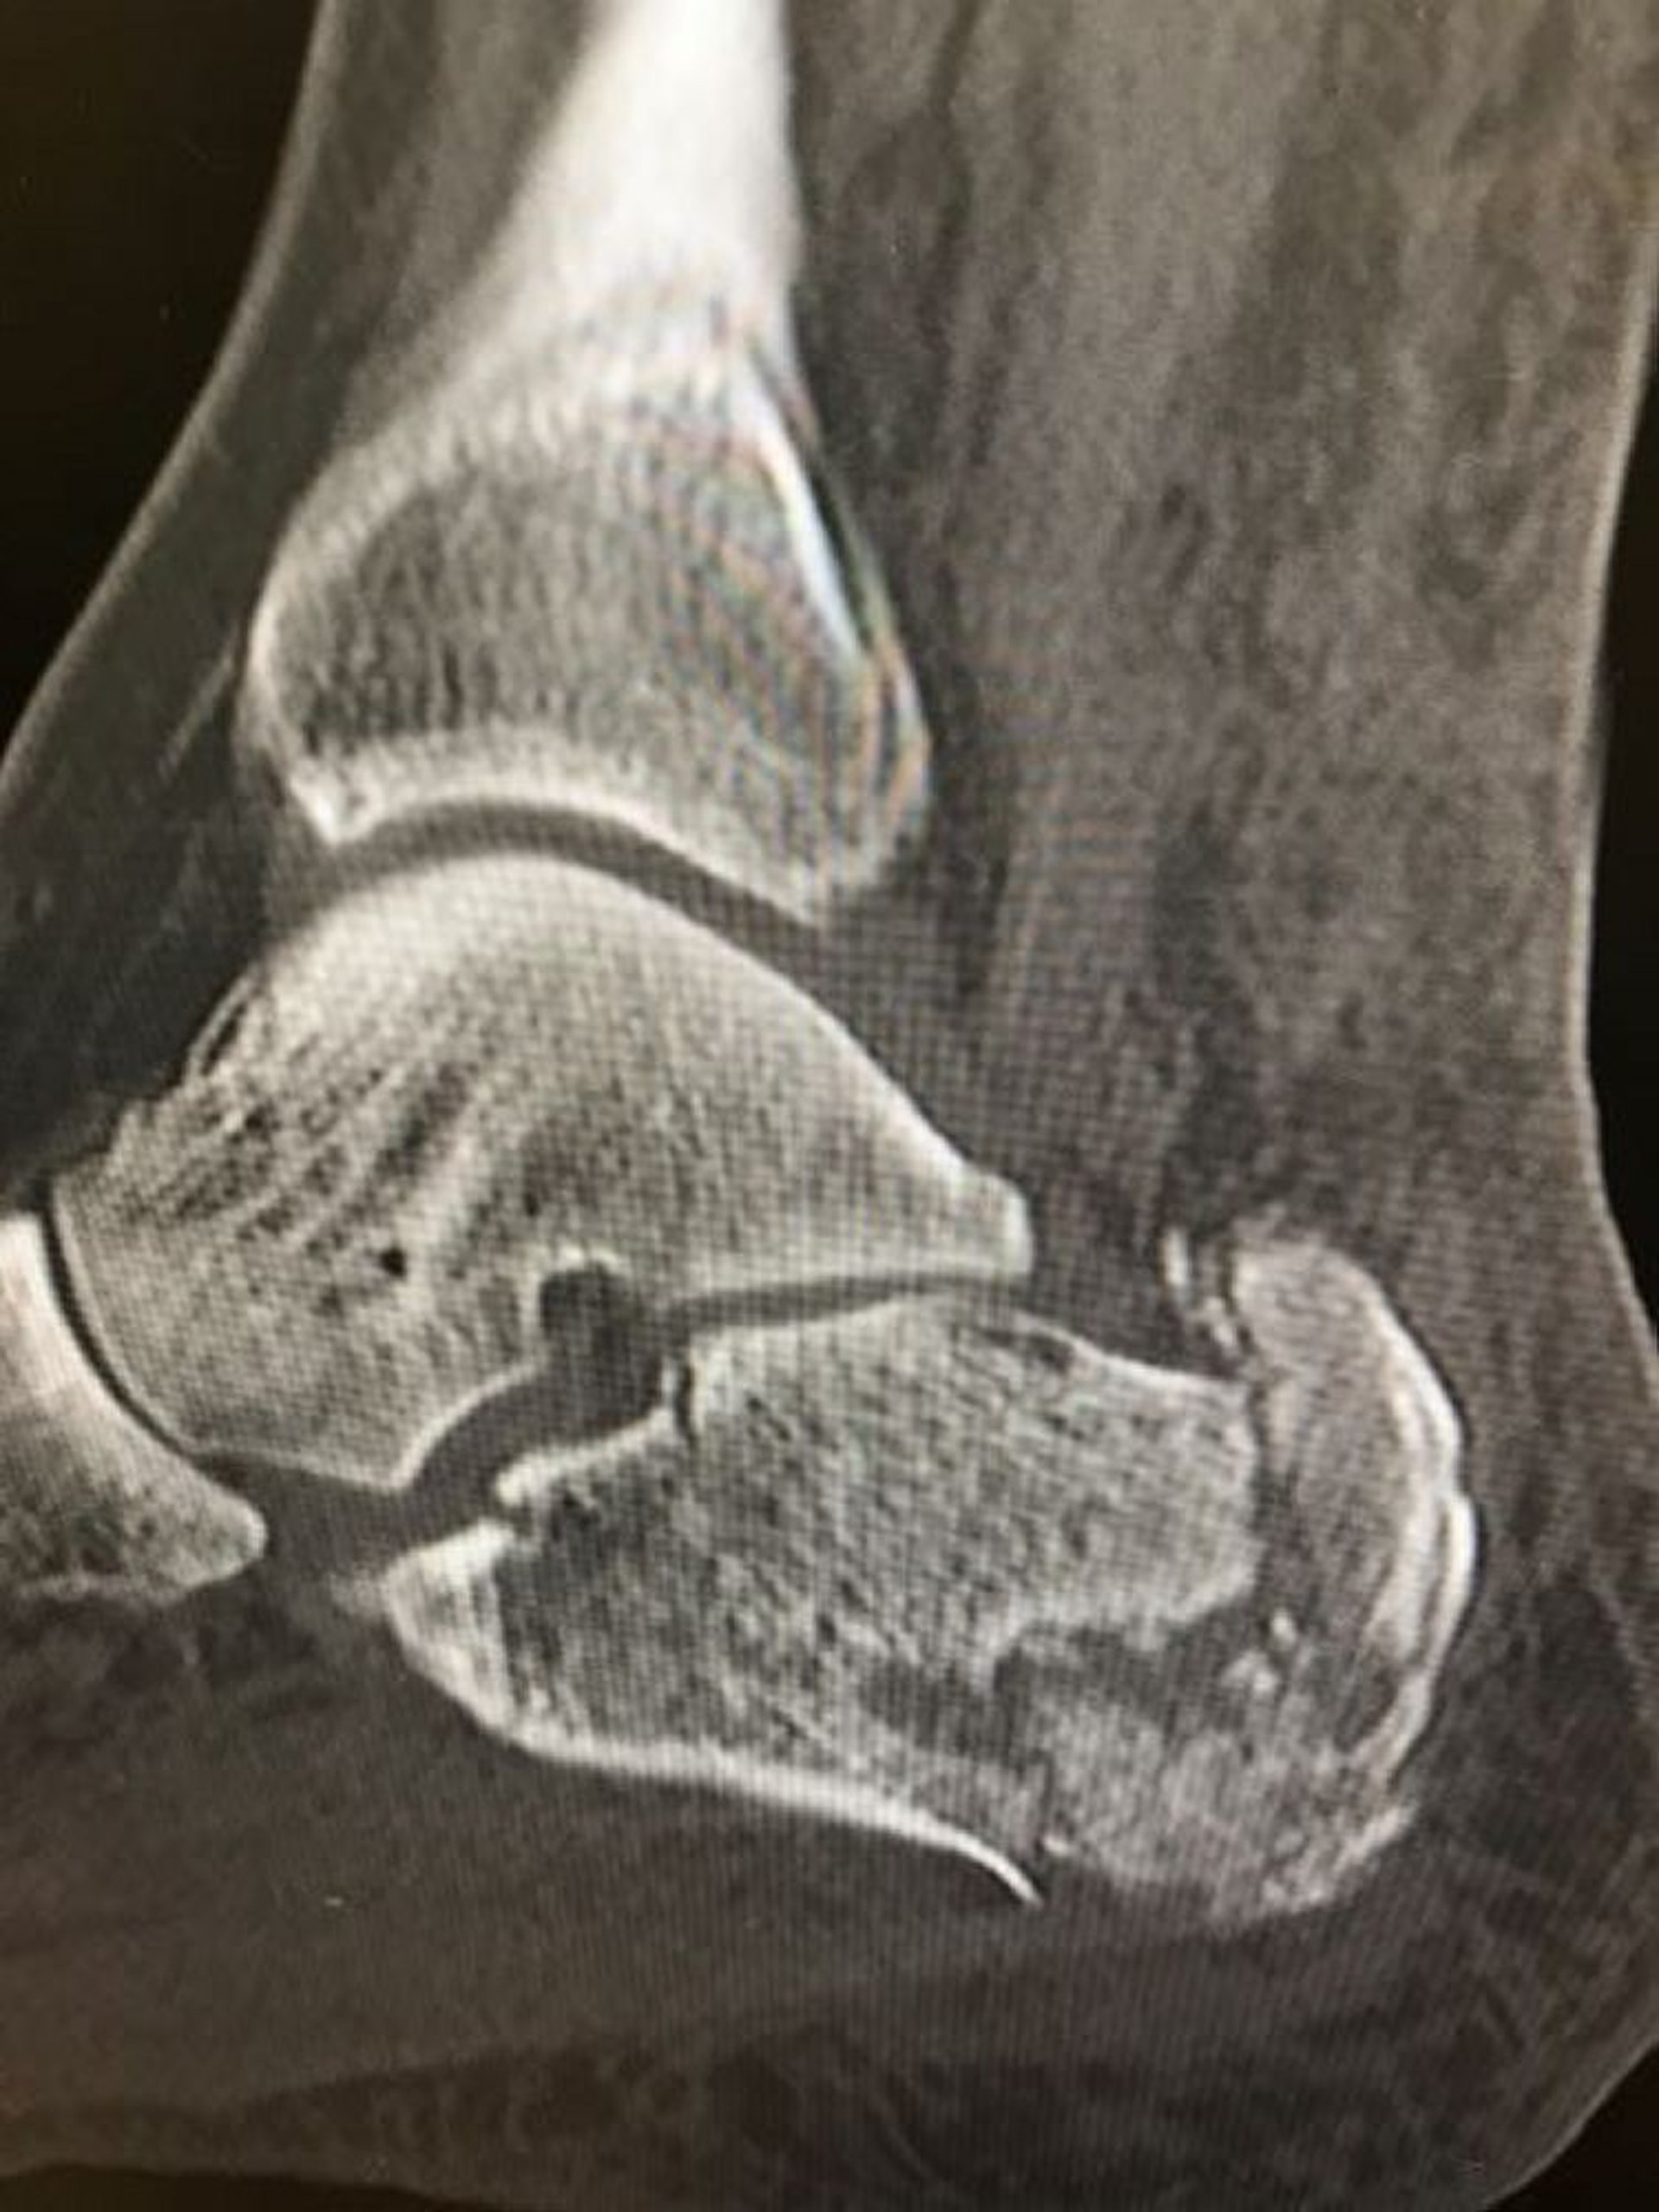

Esta radiografia mostra uma fratura cominutiva do calcâneo.

Imagem cedida por cortesia de Danielle Campagne, MD.